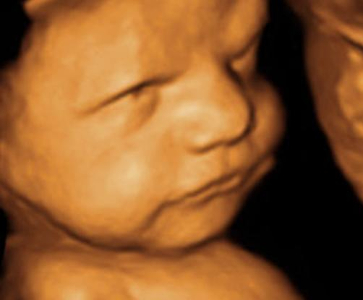

We have highly advanced Alpinion Ecube-7 3D/4D Ultrasound system, AGFA 10X CR System and 500 mA GME Radiography machine for radiology services. We have computerized pathology laboratory with highly advanced machines such as 'Sysmex XP-100', 'Erba Chem 7' and 'Automatic Hormone Analyzer'.

3D/4D Ultrasound

Having earned his MBBS from the LTM Medical College, Sion Hospital Mumbai (the most prestigious medical college in Western India). He did his Post-graduation in Radiodiagnosis (D.M.R.D.) from the prestigious Rajendra Institute of Medical Sciences (Ranchi). He has also completed 2 years Secondary DNB training in Radiodiagnosis from Lokmanya Hospital, Pune. Subsequently, he worked as Consultant Radiologist in Jaipur Golden Hospital, Rohini and other private diagnostic centres in Delhi. He has very vast experience of working on MRI, Multislice CT scan, PET CT, Ultrasound, Mammography and diagnostic X-Rays. He has special interest in Musculoskeletal MRI and Obstetrics Ultrasound.